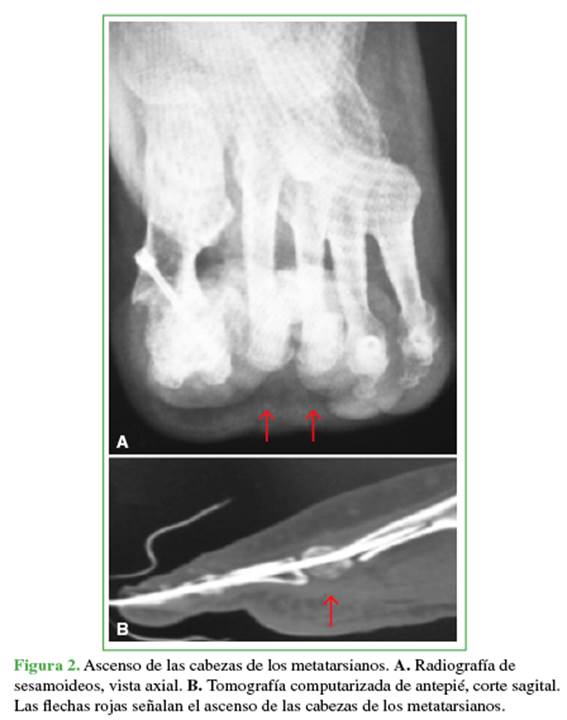

A continuación, se realiza la OMDP en la metáfisis distal con un ángulo aproximado de 45° en relación con el piso. Esta se efectúa de distal dorsal a proximal plantar para lograr el ascenso y acortamiento de la cabeza del metatarsiano, finalmente se avanza la clavija de Kirschner hacia la diáfisis del metatarsiano (Figura 1). Así, se busca disminuir la presión ejercida por las cabezas metatarsianas contra el piso (Figura 2). Por otra parte, se eleva el centro de rotación para que los músculos intrínsecos actúen nuevamente como flexores de la articulación metatarsofalángica, intentando disminuir la incidencia de dedo flotante. Para finalizar se realiza la tenotomía percutánea del flexor largo del dedo tratado para prevenir la posterior progresión a dedo en mazo.